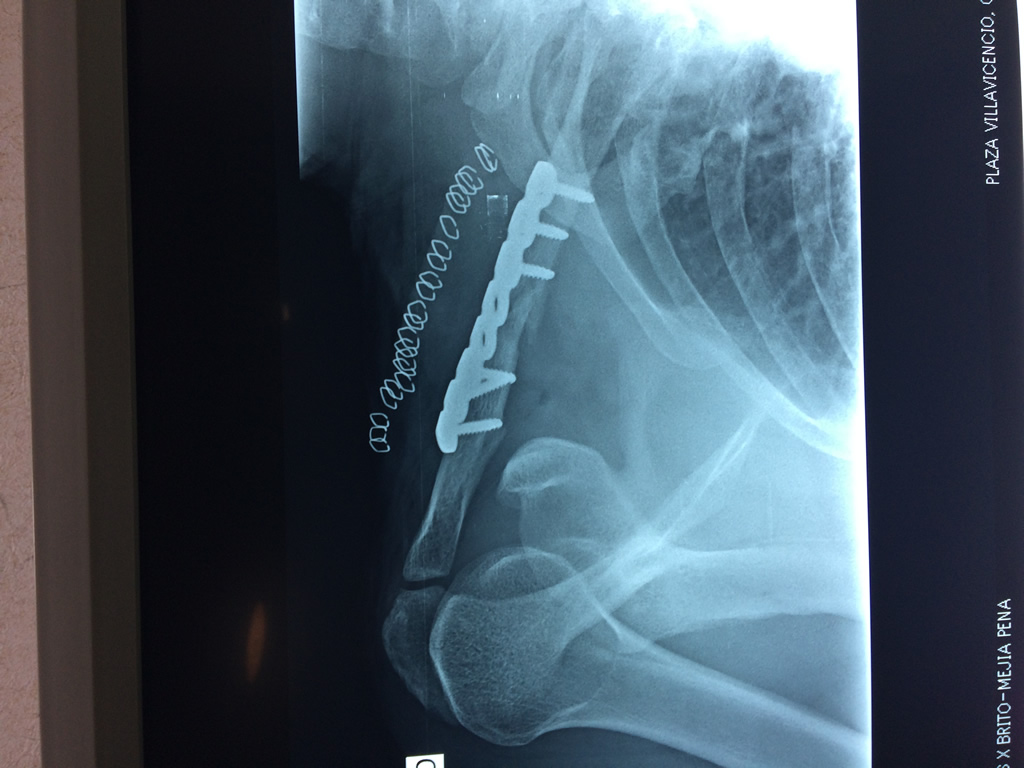

Cirugías de Calcaneo - Clavícula